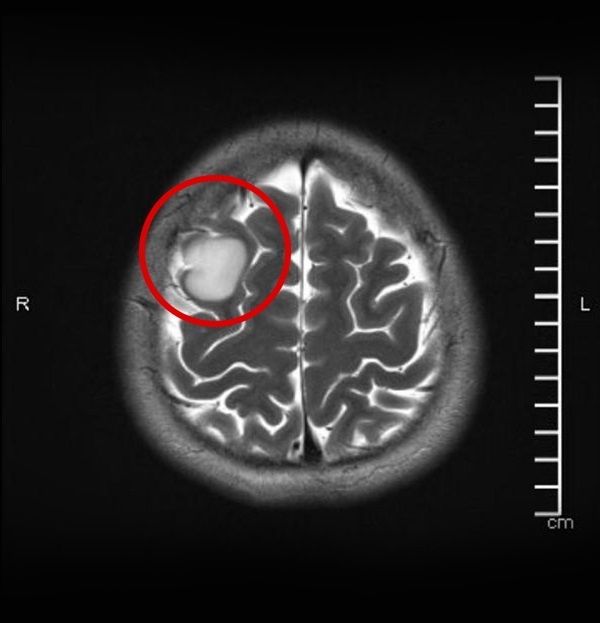

Hình chụp MRI ở 2 mặt cắt hộp sọ. |

Qua thăm khám và chỉ định chụp MRI, bác sĩ nhận thấy khối choán chỗ trong trục vùng trán phải, kích thước khoảng 2,5 cm. Tiên lượng đây là khối u sao bào độ ác tính thấp, bác sĩ Chu Tấn Sĩ tư vấn bệnh nhân nhập viện để phẫu thuật.